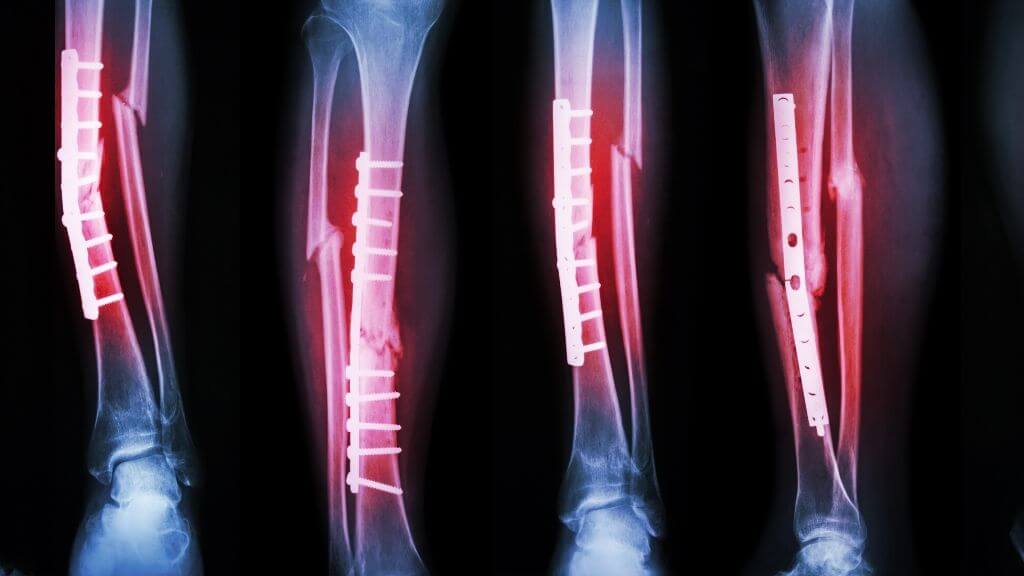

Treatment for fractures typically involves immobilization using casts or splints to allow the bone to heal naturally. In some cases, surgical intervention may be required to realign the bones and stabilize them with metal plates, screws, or rods. Physical therapy is often recommended during recovery to restore strength and mobility to the affected area.